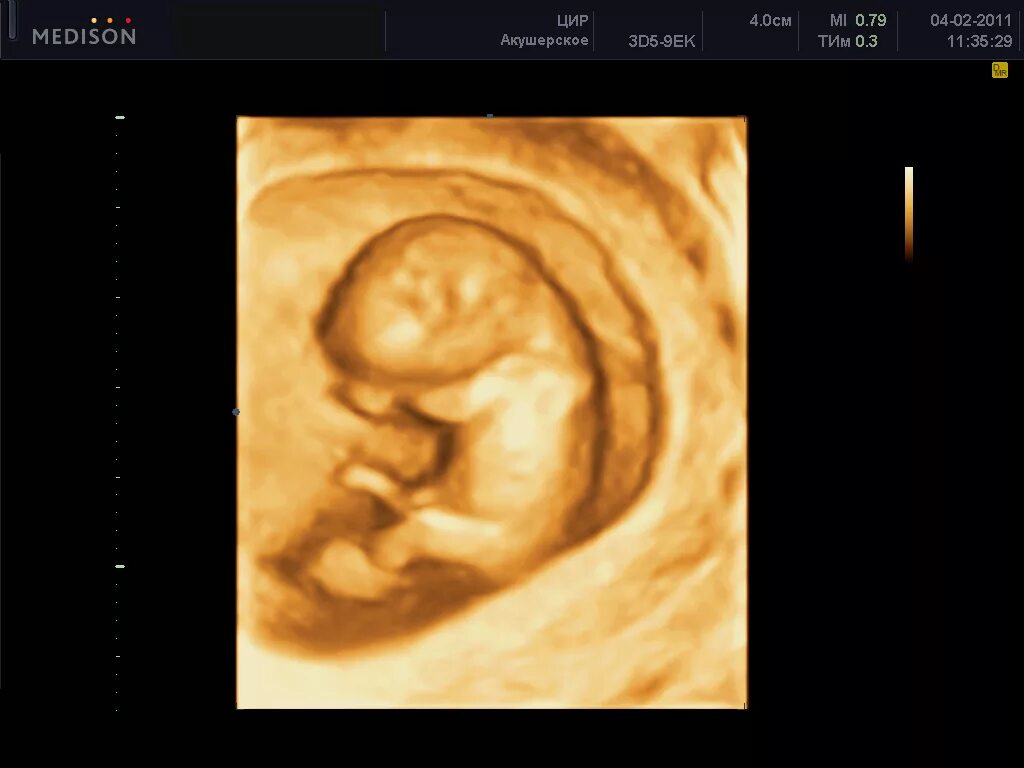

1 9 неделя беременности